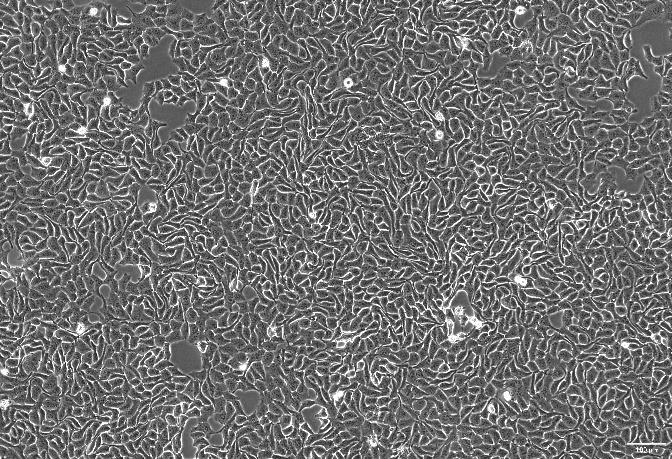

人咽头癌胸水转移细胞系(Detroit 562)是从一名白人女性咽头癌患者的咽部分离得到的上皮细胞。细胞表现出角蛋白的基因表达并通过免疫过氧化物酶染色显示对角蛋白阳性。

贴壁生长;上皮细胞样